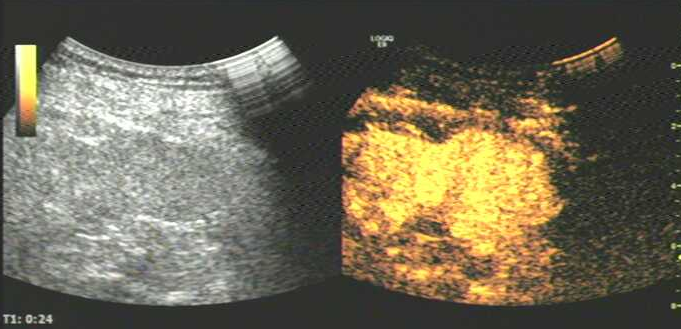

图片7.png

造影剂注射后24秒,肾内病灶内及肾实质增强达峰值,病灶呈整体均匀高增强;